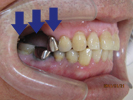

50代女性

![]() |

治療前 |

||

治療中。仮歯。 左上の奥にインプラント埋入。 噛みあわせ治療を行いました |

治療後 全体の歯で食事がおいしくできるようになったと喜んでおられました。 |